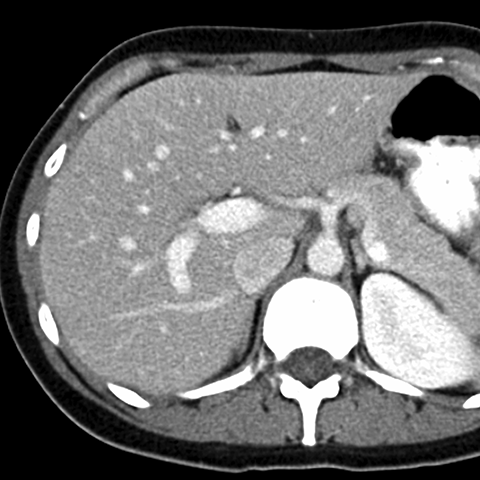

Normal Liver, CT ( axial ) [6 of 9]